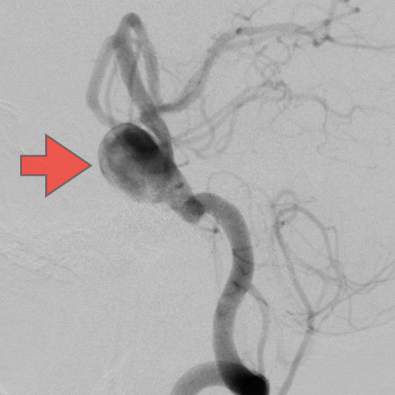

当科で治療した年々大きくなった大型脳底動脈瘤の3次元脳血管撮影像です。脳動脈瘤と周囲の血管の状態が非常によく分かるため、術前に十分な検討が可能でした。

術前

術後、脳底動脈瘤はコイルにより完全に塞栓され、正常の脳底動脈の血流は維持されている。